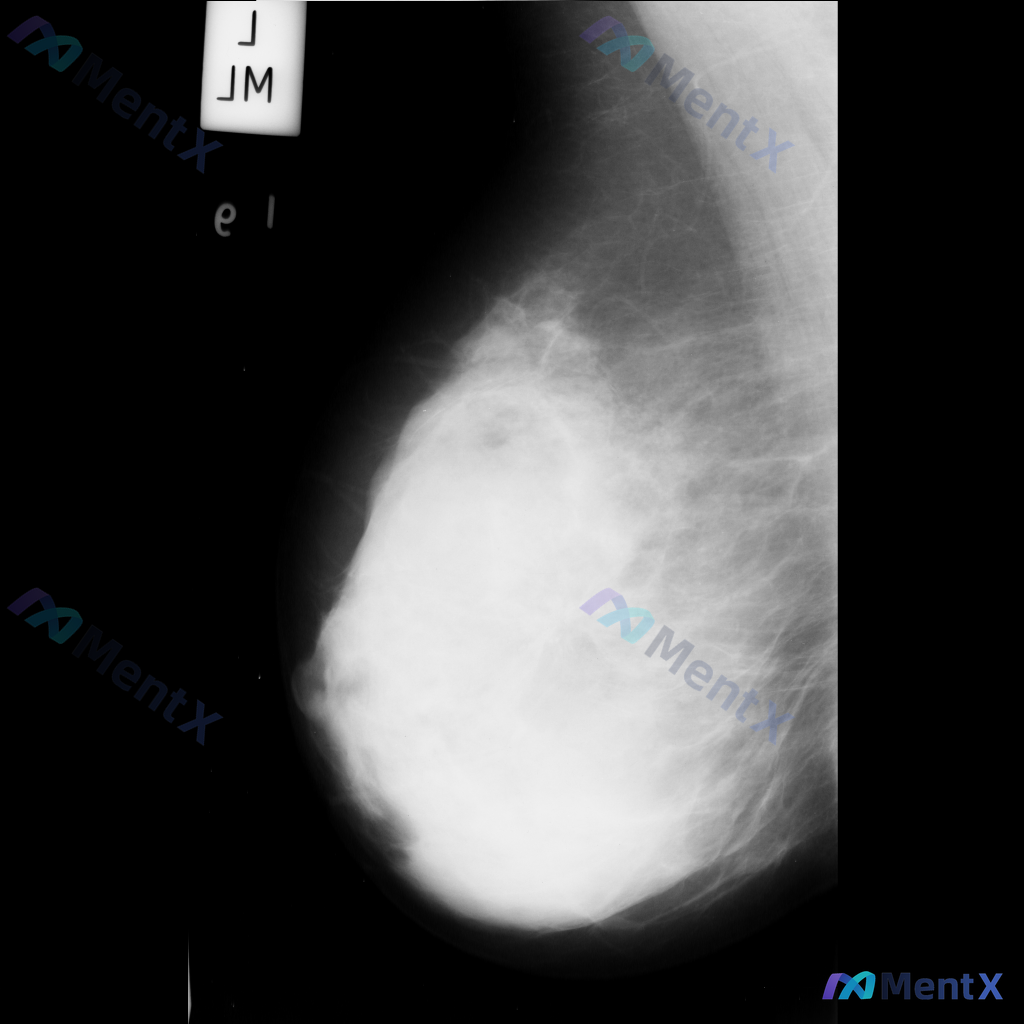

整理到一张乳腺钼靶影像的讨论资料,右乳可见一处病灶。 想先请大家看看:针对这张影像的异常表现,用什么术语描述最准确全面?另外结合征象,第一反应会往哪个方向考虑?

整理到一张乳腺钼靶影像资料,可见一处明确的异常表现: - 局部有形态不规则的占位性病灶,密度高于周围正常腺体组织 - 病灶边缘有细小的放射状结构向周围延伸 - 病灶周围的乳腺腺体和纤维组织结构排列紊乱 另外,该病例的乳腺组织整体密度较高(不均匀致密型)。 想和大家讨论:对于这张影像的异常表现,用哪些...